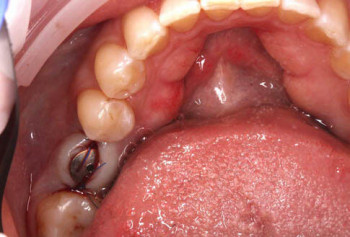

3 работы в портфолио